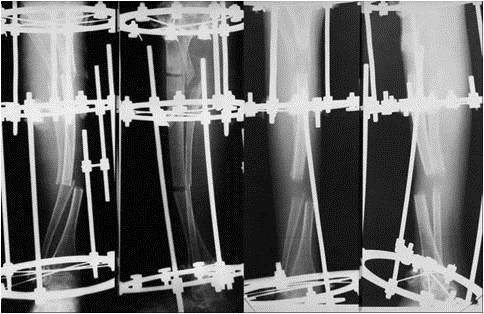

In the above-mentioned period, from the OI patients who are in the evidence of our clinic, 32 were operated on, totaling 81 surgeries. Out of these, 28 patients, aged 2-27 years, have benefited from reconstructive surgery of the pelvic limbs. Sofield-Millar osteotomies were practiced and 69 Sheffield telescopic rods were implanted in 25 patients and 43 surgeries. The coxa vara / valga correction using the Sheffield rod was applied in 6 patients and 8 hips, respectively. Circular or monoplane external fixators were used in 7 patients for the correction of deformities, lengthening and arthrodiastasis. 9 patients have benefited from various forms of bone transplant: pedicled grafts, auto- and/or allografts. An original bone reconstruction procedure is currently being studied and will be useful in the treatment of large bone defects and the thickening of the gracile diaphyses, which consists in practice of a massive contribution of free bone grafts, auto- and/or allogenic, bone substitutes and, in selected cases, periosteal substitutes, in a composite stratified construction. Postoperatively, 15 patients are able to walk while being supported by crutches or walking frames, 5 patients walk independently and 8 are still wheelchair-bound. It is important to mention that 8 children who were preoperatively dependant on the wheelchair are now walking!

在上述期间,在我们诊所登记的OI患者中,有32人接受了手术,共计81次手术。其中,28名年龄在2至27岁的患者接受了骨盆四肢的重建手术。实施了索菲尔德 - 米勒截骨术,并在25名患者的43次手术中植入了69根谢菲尔德伸缩杆。分别对6名患者的8个髋关节应用谢菲尔德杆进行了髋内翻/髋外翻矫正。7名患者使用环形或单平面外固定器进行畸形矫正、肢体延长和关节扩张。9名患者接受了各种形式的骨移植:带蒂移植、自体和/或异体移植。目前正在研究一种原始的骨重建程序,该程序将有助于治疗大的骨缺损和纤细骨干的增厚,其实际操作是大量使用游离骨移植、自体和/或异体骨替代物,以及在特定情况下使用骨膜替代物,进行复合分层构建。术后,15名患者能够借助拐杖或助行架行走,5名患者能够独立行走,8名患者仍需依赖轮椅。需要提及的是,8名术前依赖轮椅的儿童现在能够行走了!